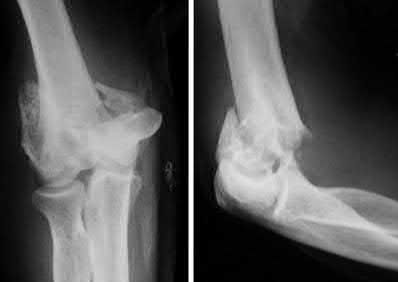

A 72-year-old woman falls down stairs and sustains the injury shown in Figure A. Additional radiographs are performed in Figure B to help assess the fracture pattern. These additional radiographs represent which of the following?

Additional traction radiographs are performed in distal humerus fractures to better understand the fracture configuration.

Traction radiographs help align the fracture fragments for better visualization. This is useful in comminuted fractures where distal fragments are telescoped or flexed on the proximal fragments, making CT scan visualization difficult.

Proper visualization can help determine (1) the approach to the distal humerus, (2) whether to perform ORIF or total elbow arthroplasty (in select patients), (3) whether to add a 3rd plate (lateral column), (4) whether to add tricortical bone graft to augment distal fixation and restore trochlear width.

Figures A and B show a distal humerus fracture without traction (A) and with traction (B) applied. Illustration A shows the same fracture after bicolumnar plating. Illustration B shows the different surgical approaches to the distal humerus (A, Campbell triceps splitting; B, O'Driscoll triceps reflecting anconeus pedicle [TRAP]; C, Bryan-Morrey triceps reflecting; D, olecranon osteotomy)